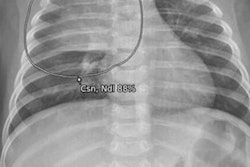

Under the terms of the deal with the Korean National IT Industry Promotion Agency, Lunit will deliver its Insight CXR software to more than 30 Korean military medical sites by the end of 2022. The software detects nine types of abnormalities via chest x-ray and aims to better detect critical lung diseases, including tuberculosis.